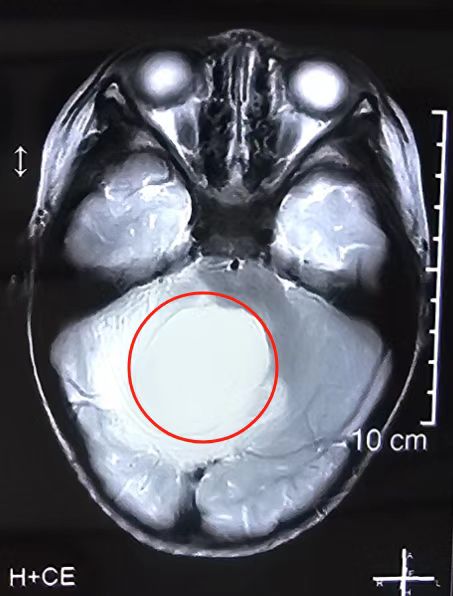

一个直径达5公分的巨大肿瘤,藏匿于2岁男童的第四脑室,严重威胁幼小的生命。近日,武汉大学人民医院(湖北省人民医院)神经外Ⅲ科徐海涛教授团队迎难而上,历时11小时为患儿摘除颅内巨大肿瘤。6月4日,患儿康复出院。

5月中旬,湖北仙桃2岁10个月的晨晨(化名)突然出现间断性的恶心呕吐。起初,家人以为只是吃坏了东西,但连日来,这样的症状不仅反复出现,还不断加重。当地医院头部磁共振检查显示“脑干背侧、四脑室巨大肿瘤性病变”,同时伴有脑积水,考虑恶性髓母细胞瘤可能性大,病情非常严重。为寻求一线生机,一家人慕名找到武汉大学人民医院神经外Ⅲ科副主任徐海涛教授。

入院后,徐海涛教授团队迅速组织多学科会诊,并进行了详细的术前评估与准备。由于第四脑室解剖结构复杂,底部为人的“生命中枢”脑干,手术操作必须非常细致和精准,稍有不慎就有可能出现术后昏迷、瘫痪、呼吸衰竭甚至死亡的严重后果,手术风险大且难度高。但患儿病情进展快,如果不尽快手术切除,肿瘤对脑干的压迫会逐渐加重、危及生命。与患儿家长充分沟通后,家长决心放手一搏。